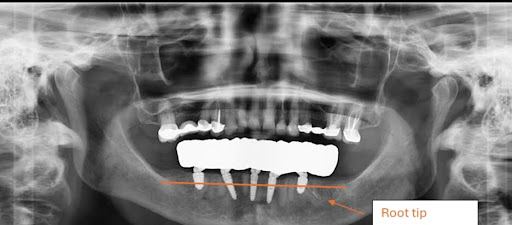

A patient came in for a consultation at our clinic in Temecula the other day, wanting All-on-X dental implants for her upper teeth. She recently had a lower All-on-X procedure completed at another office in town. Immediately upon seeing the X-rays, we understood that there was nothing we could do for this patient. Her first surgery was botched so badly that doing the upper surgery would mean simply building on a suboptimal foundation and giving the patient a terrible outcome.

So what exactly went wrong with her All-on-X surgery? Simply put, the surgeon who did the original lower jaw surgery did it incorrectly. The lower jawbone was not prepared well to receive a full arch prosthesis. Normally, the lower jawbone should be adjusted after the teeth are removed by creating a uniform platform at the appropriate height to house the new final prosthesis. The final prosthesis needs to be at least 15 mm tall (just over half an inch) to ensure appropriate strength and stability. You can’t fit a 15 mm prosthesis where natural teeth were before without reducing the bone underneath.

Well, apparently, her surgeon didn’t get that memo. He simply removed the teeth and then placed All-on-X dental implants at the same level where the teeth were before. Now, adding a 15 mm thick prosthesis on top results in the patient’s upper teeth getting hammered and smashed constantly because the prosthesis is too big and is violating the restorative space.